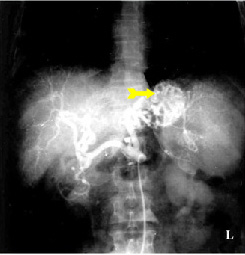

בחולים שמצבם הקשה כרוך בסיכון ניתוחי גבוה, ניתן לבצע ארטריוגרפיה ברירנית של עורקי הקיבה, לזהות את מקור הדימום, ודרך צנתר האנגיו להכניס חומר מטרש כמו דם קרוש, Histoacryl וכו', ולהזריקו לעורק כדי שיסתום את כלי הדם המדמם ויעצור את הדימום עד לייצוב החולה והכנתו לניתוח (תצלום 7.3).